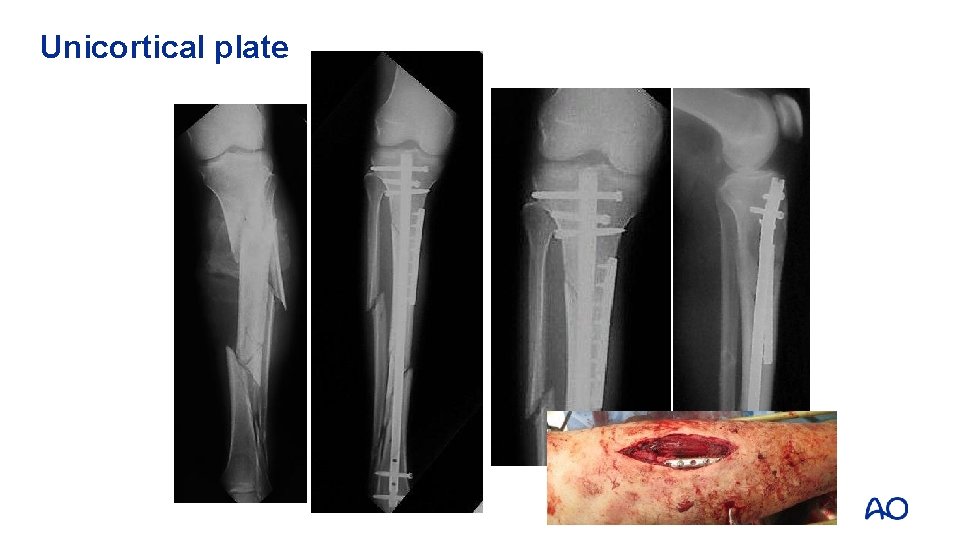

Techniques to avoid malreduction • Correct starting point • Central and proximal • Nail in extension • Blocking screws • Unicortical plating

Unicortical plate